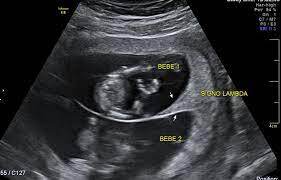

Aspectos ultrasonográficos a tomar en cuenta durante la evaluación de la corionicidad de embarazos múltiples

• Signos “Lambda” (bicorial) o de la “T” (monocorial)

Consiste en la presencia de tejido placentario entre las membranas de ambos sacos amnióticos e implica que se trata de una gestación bicorial

Signo lambda